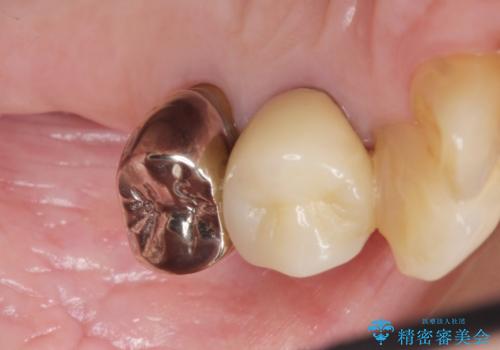

クラウンの種類:オールセラミッククラウン スタンダード

気にされていた歯の動揺や違和感がなくなり、喜んで頂けました。

モチベーションがあがり、大臼歯欠損部位の治療に関しても前向きに検討して下さるとの事でした。